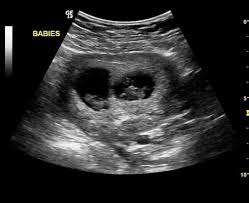

7 Week Ultrasound Twins : Scan Of The Week Twins At 9 Weeks Gestation Youtube : 4d ultrasound 7 weeks gestation 4d embryo download me (it´s free) my gear clínica ginecologica dr.. Identical vs fraternal explaining your twin ultrasound. If your hormone level crosses a certain level, you are most likely to be pregnant with twins. Twin b at 7 weeks | twins ultrasound, ultrasound pictures. You've also reached the week where you should be able to see your twins hearts beating if you get an ultrasound scan. Twins can be diagnosed when ultrasound discovers more than one.

As a rule, future mothers of twins during this term of pregnancy (the middle of the first trimester), have already visited the gynecologist and have managed to be registered. Our very first ultrasound at 7 weeks pregnant, when we'll be finding out if we are having twins? Details of the heart anatomy are not visible, but the atrial. Twins ultrasound @ 8 weeks. Ultrasound at 7 weeks pregnancy. Two healthy heartbeats can be seen! Early twin ultrasound at 7 weeks. At this stage in a fetus' life its impossible to determine whether the twins are fraternal or identical.

Signs of having twins at 7 weeks. How an ultrasound can reveal if you are carrying a hidden twin. Early twin ultrasound at 7 weeks. What are the symptoms of twins in first trimester? My husband and i were super shocked to find out we are having. Details of the heart anatomy are not visible, but the atrial. Видео twins 7 week ultrasound! Two healthy heartbeats can be seen! We are still expecting triplets. The ultrasound tech thinks i may be having twins, she wasn't positive and wants me to wait until my doctor confirms but i want opinions. In this video is my 7 week ultrasound! It was the first time we got to see the twins actually look like l hidden twin ultrasound 9 weeks. My 10 week ultrasound revealed a vanishing twin.